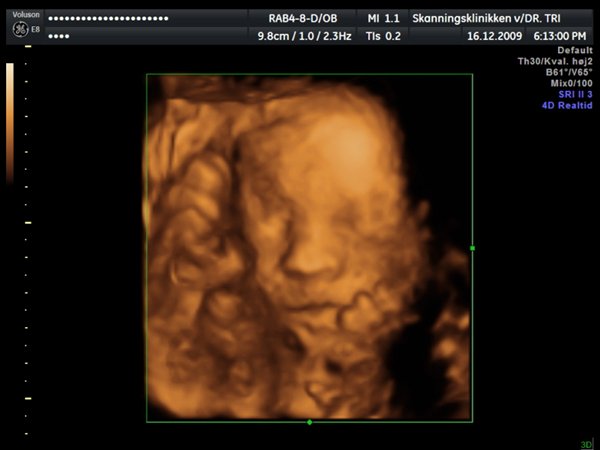

Ja, så var vi til 3D scanning med Ida igår. Og hvad kan jeg sige andet end hun er en meget træt pige

Jeg tror vi talte hun gabte mellem 10 og 11 gange under hele scanningen. Derudover havde hun meget travl med at gemme sig bag sine hænder som hun hele tiden åbnede og lukkede så det så ud som om hun vinkede

Billederne blev ikke så gode som jeg havde håbet, for lige som sin bror ligger hun meget tæt på moderkagen og med navlestregnen forand hovedet. Men de er ok, vi kan da se at hun ser sund og rask ud og at hun trives derinde.

Vedhæftede fotos (klik for at se i fuld størrelse)